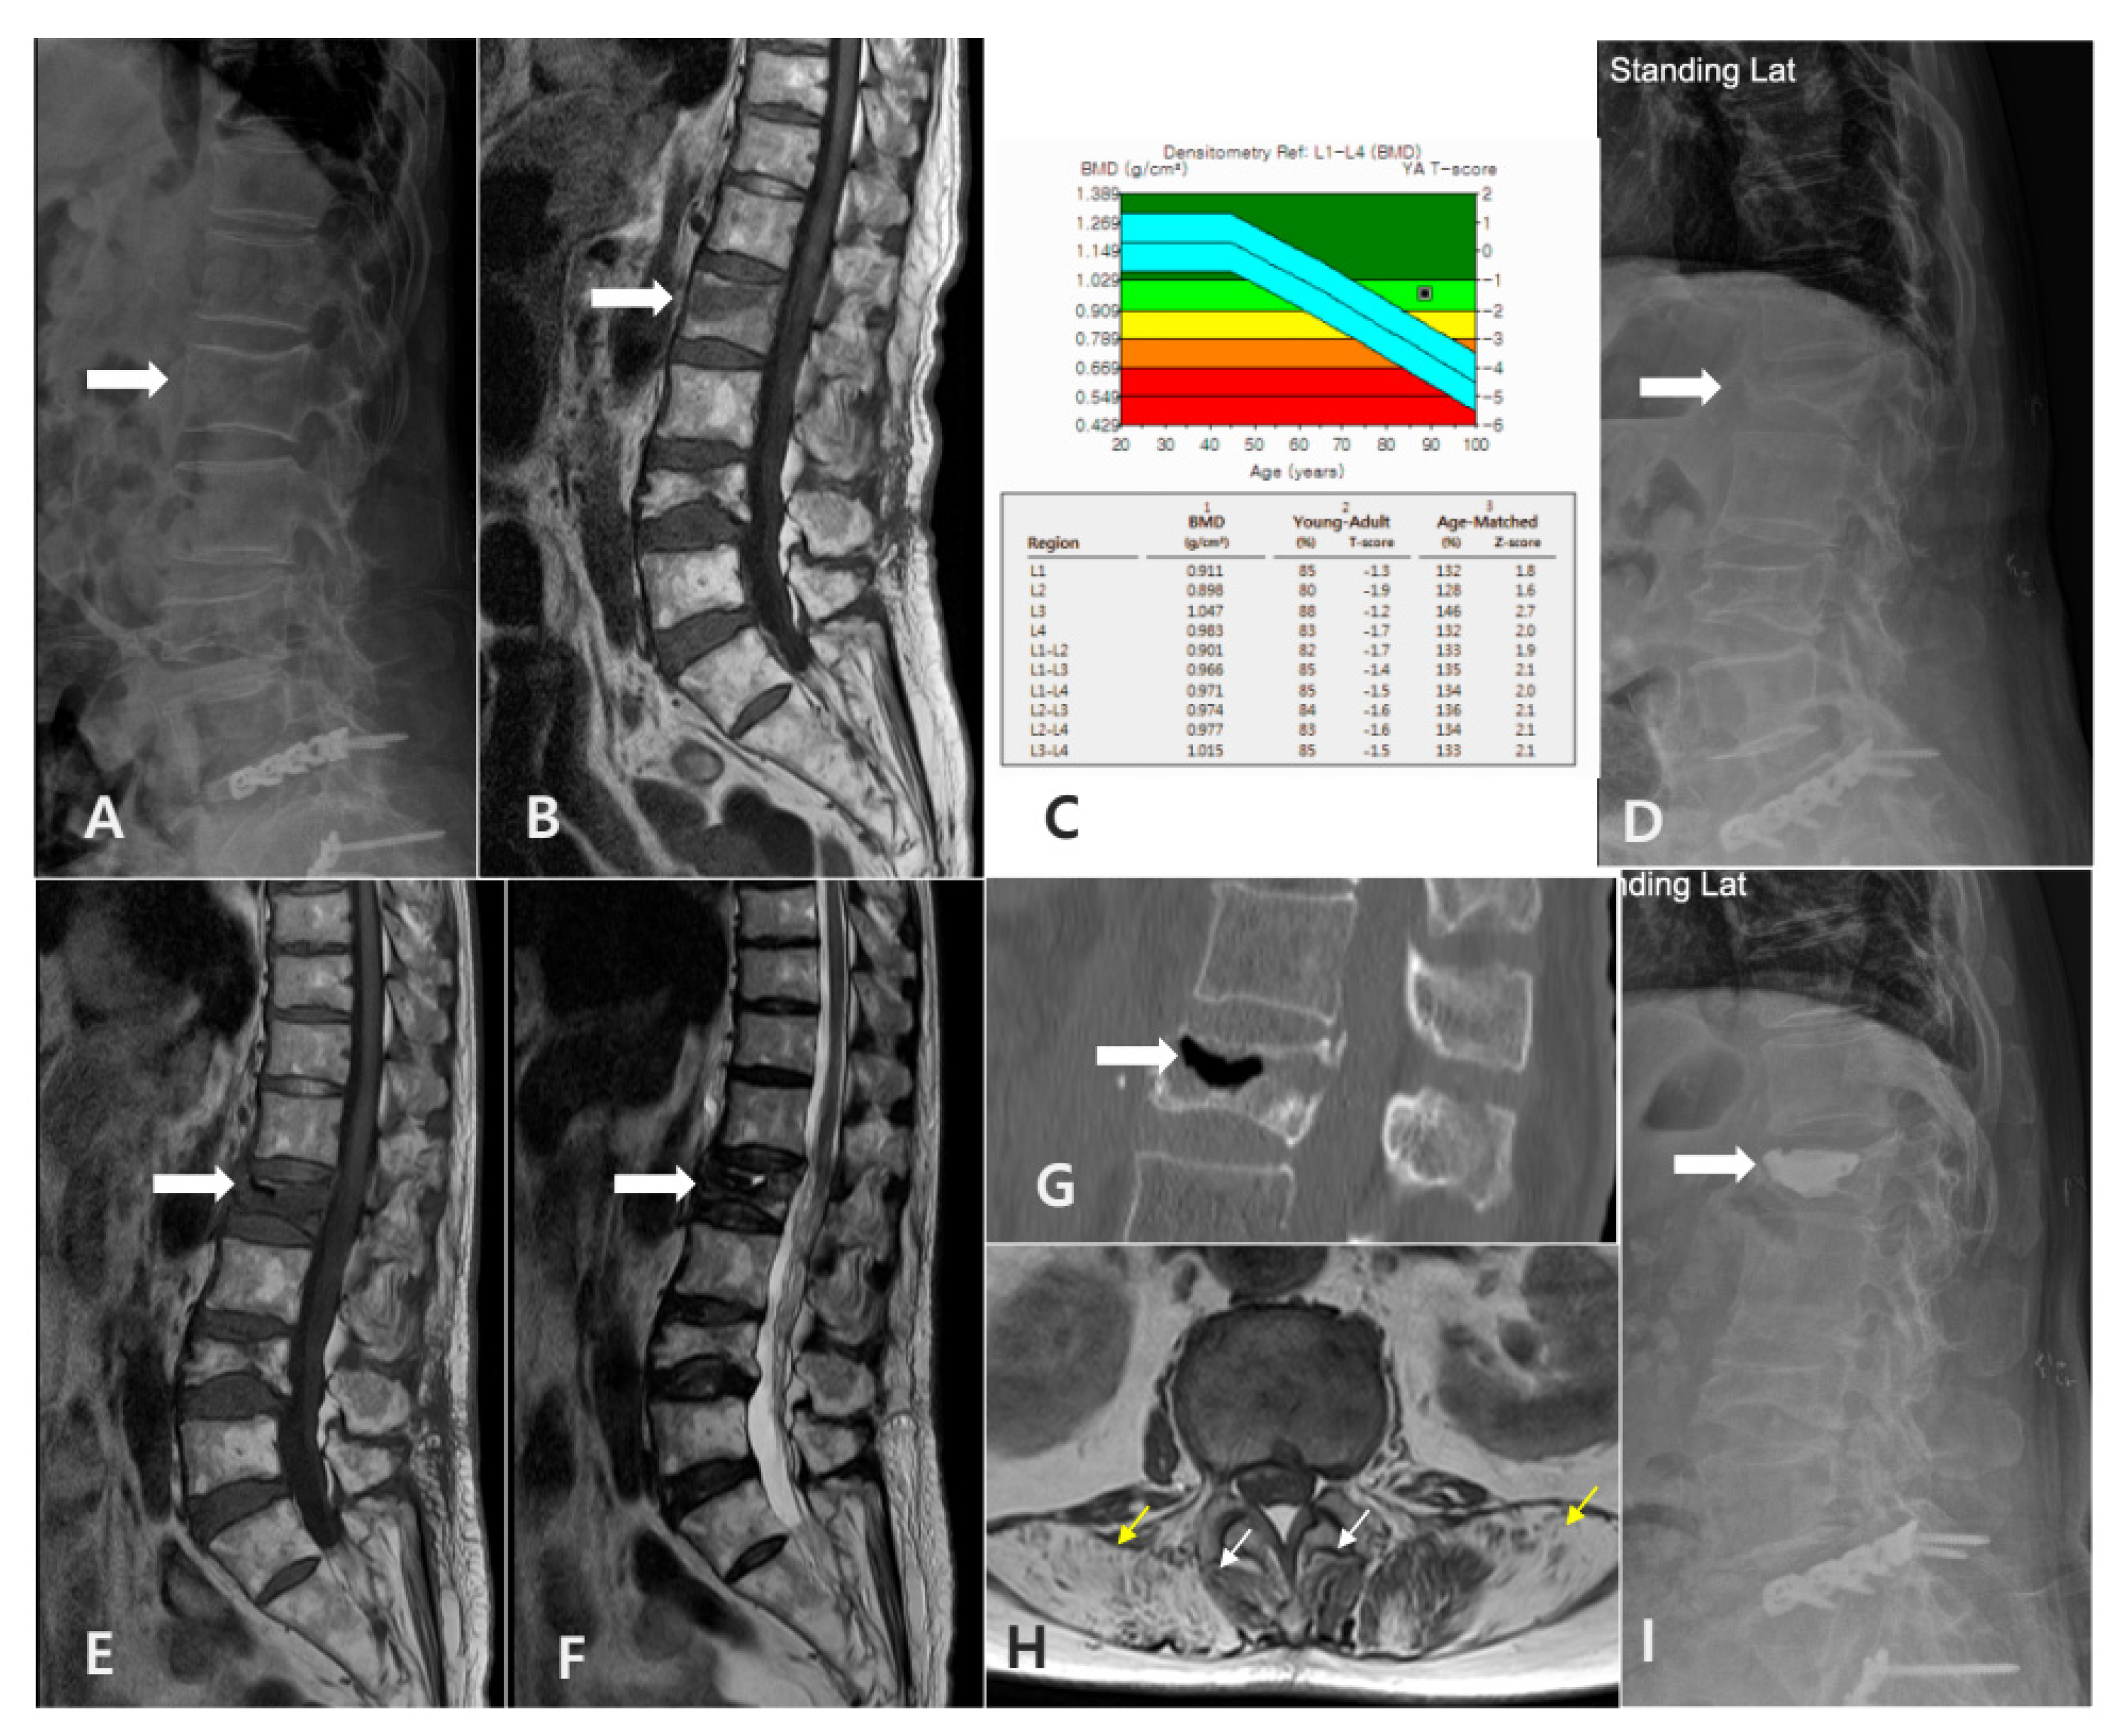

2.2. Definition and Diagnostic Criteria of SIVC

- Radiographic Criteria:

- -

- Radiographic evidence of intravertebral vacuum cleft (IVC) on plain thoracolumbar radiographs.

- -

- Absence of other significant pathology at the affected and adjacent levels, such as new fractures.

2.3. Data Collection